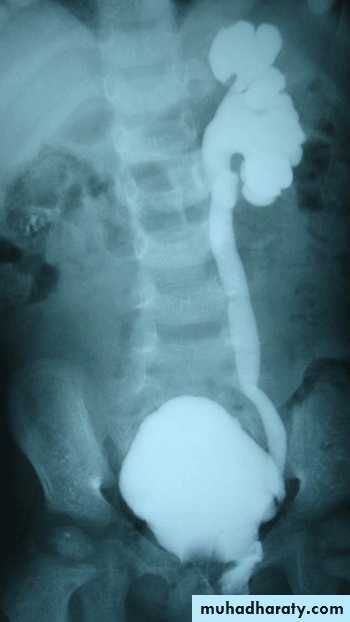

US: pre- and post-natal.IV Urography

Isotope renal scan.

VUR is classified into 5 grades depending on the severity of reflux and the associated dilatation of the renal system.